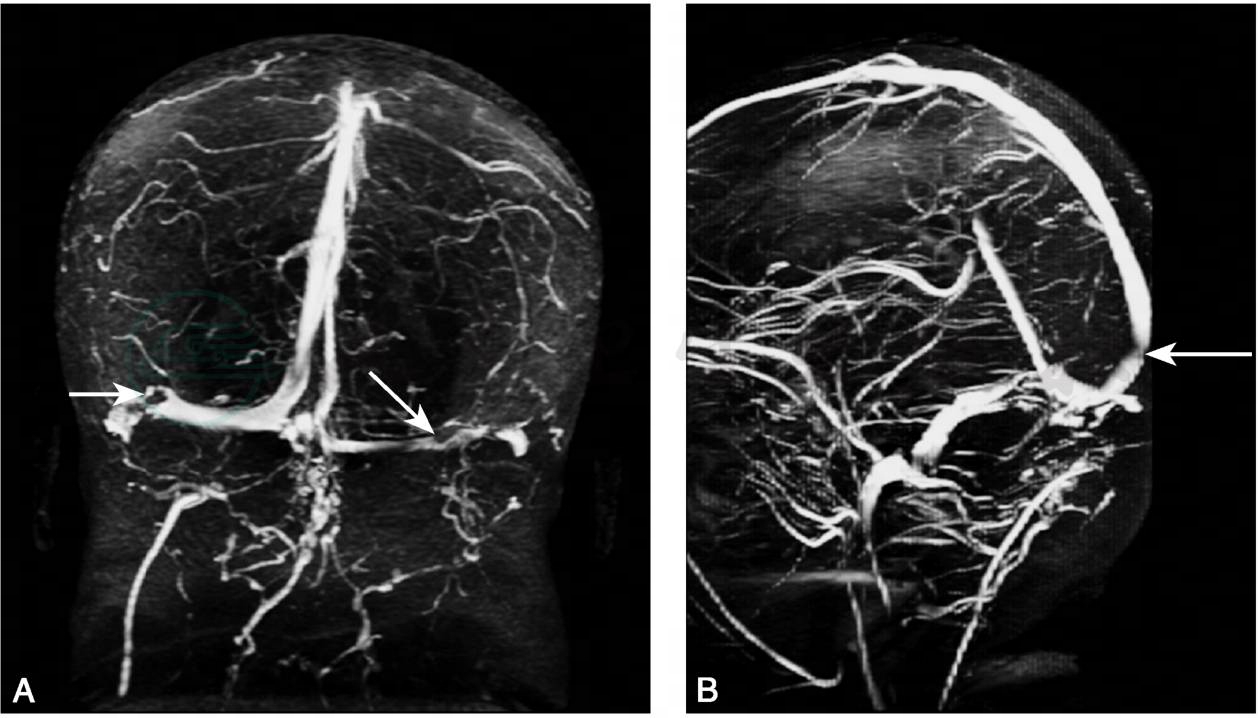

颅脑MRI(2011年4月11日):右侧额叶皮层下脑白质点状脱髓鞘改变(图1)。颅脑MRV (2011年4月14日):①双侧横窦血流信号变细减弱,血栓形成可能性大;②上矢状窦内信号不均,血栓形成不除外(图2)。

图2 颅脑MRV(2011年4月14日)

A.双侧横窦血流信号变细减弱,血栓形成可能性大(箭头);B.上矢状窦内信号不均,血栓形成不除外(箭头)

患者入院后出现头痛、呕吐(2011年4月10日),查颅脑MRV(2011年4月14日)提示:双侧横窦、上矢状窦血栓形成可能性大(见图2)。考虑诊断颅内静脉窦血栓形成,给予低分子肝素皮下注射(0.3ml 12小时一次)抗凝1周后改为口服氯吡格雷75mg每日一次抗栓治疗(因考虑患者出院后缺乏监测凝血指标的条件故未使用华法林)、甘露醇脱水降颅压治疗(腰穿颅内压280mmH2O),经治疗患者头痛、呕吐完全缓解。复查腰椎穿刺(2011年4月22日),压力160mmH2O,脑脊液常规、生化均正常。